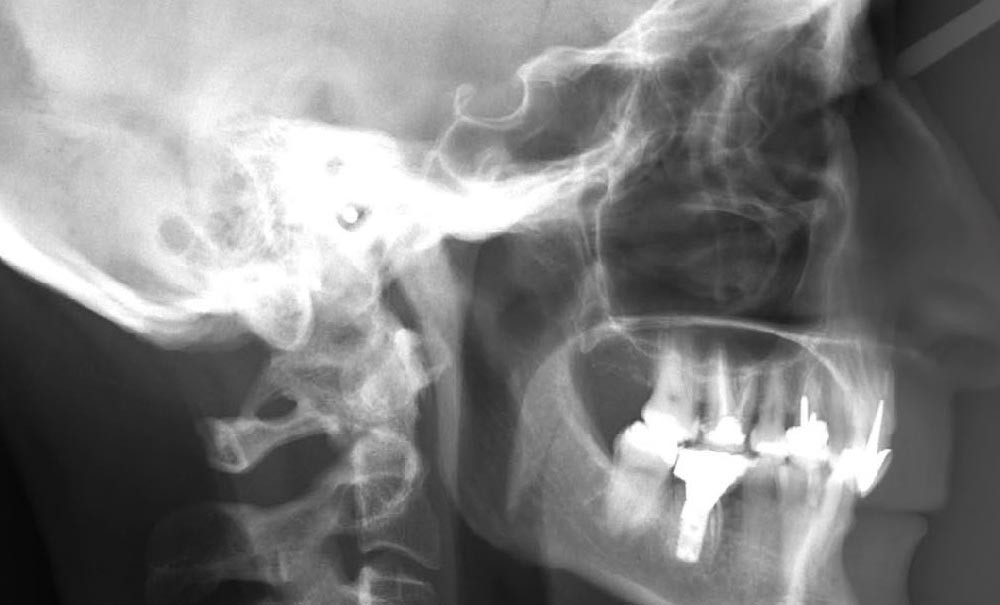

Examens complémentaires (fig. 3)

La téléradiographie de profil et l’analyse céphalométrique montrent une classe I squelettique tendance classe II dans un contexte d’hypodivergence avec diminution de l’étage masticatoire. L’axe de l’incisive mandibulaire est en normoposition, alors que l’incisive maxillaire présente une rétroalvéolie importante.

La supraclusion antérieure est d’origine mandibulaire en lien avec une courbe de Spee marquée quantifiée à 3 mm. L’orthopantomogramme confirme la présence d’un implant en 36.